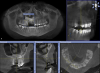

Ашот Опубликовано 8 октября, 2012 Поделиться Опубликовано 8 октября, 2012 Уважаемые коллеги, ситуация в следующем. Я хирург, хочу услышать мнение ортодонтов.Пациент 25 лет. Зуб 53 удален в детстве. В 23 года начал носить брекеты, пытались сначала свести 14,12. Затем решили развести 12,14, с последующим наращиванием кости в области 13 и имплантацией. Все это прошло безуспешно, графт не прижился. На данный момент пациента ведем мы.Вопросы:1) возможно ли вытянуть этот клык?2) вестибулярно или небно лучше раскрыт? Сразу оговорюсь, вестибулярно попытался открыть, но наклон большой и ортодонт не решился прицепить тягу. Теперь просит открыть небно, но не уйдет ли кость, оставшаяся незначительно небно? Спасибо. 1 Ссылка на комментарий

TiAn Опубликовано 9 октября, 2012 Поделиться Опубликовано 9 октября, 2012 Кость уйдет небная, конечно. Мне кажется, это не очень благоприятное положение зуба, слишком сильный угол к основной оси зубов 11 и 12. Ссылка на комментарий